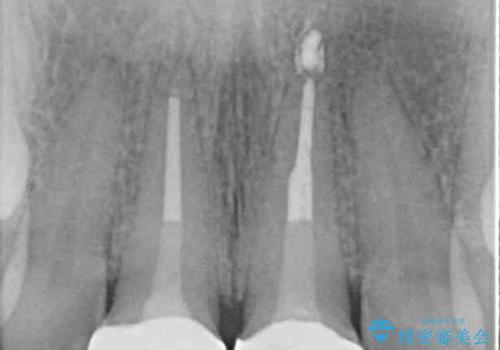

- 前歯の形と色を気にして来院された患者様です。

虫歯で神経を取り除いたことによる変色や充填物の着色などが認められたため、オールセラミッククラウンにて補綴することとしました。

また、咬耗により周囲の歯がすり減ったことで、前歯2本のみが長く見えていたため、周囲に長さを合わせることとしました。

治療を提供する側からすると、歯が短すぎるように思えますが、患者様としては長年気になっていた形態が改善され、大変満足していただきました。